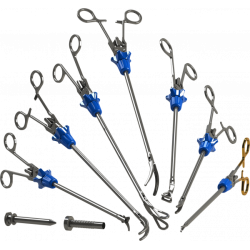

Ampla oferta de cateteres para tratamento de acesso arterial, venoso e AV em vasos variando de 1,5 mm a grandes vasos iliofemorais

Especificações de Cateter

| Modelo | Indicação | Plataforma de Liberação | Diâmetro Mínimo do Vaso | Comprimento do Cateter | Diâmetro do Cateter | Fio-guia | Power Pulse™ Habilitado | Fio-Guia Alternável | Porta de Injeção de Contraste |

|---|---|---|---|---|---|---|---|---|---|

| ZelanteDVT™ | Venoso | OTW | 6 mm | 105 cm | 8 F | 0,035” | Sim | Sim | Sim |

| Solent™ Omni | Acesso AV, Arterial e Venoso Periférico | OTW | 3 mm | 120 cm | 6 F | 0,035” | Sim | Sim | Sim |

| Solent™ Proxi | Acesso AV, Arterial e Venoso Periférico | OTW | 3 mm | 90 cm | 6 F | 0,035” | Sim | Sim | Sim |

| Solent™ Dista | Arterial Periférico | OTW | 1,5 mm | 145 cm | 4 F / 3 F | 0,014” | Sim | N/A | N/A |

| AVX™ | Fístula e Enxertos de Acesso AV | OTW | 3 mm | 50 cm | 6 F | 0,035” | N/A | N/A | Sim |